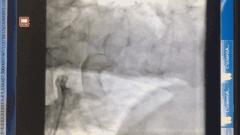

血管开通前造影